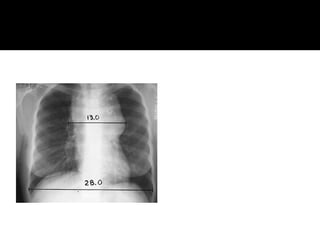

 Radiographic studies- Chest radiographs: posteroanterior and lateral; Contrast-

enhanced computed tomographic (CT ) scan of thorax, abdomen, and pelvis;

Contrast-enhanced CT scan of neck (if neck irradiation is indicated); Integrated

positron emission tomography-CT scan